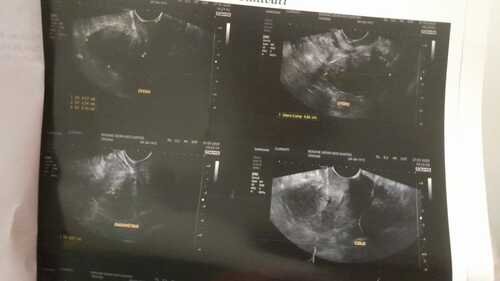

Há um mês descobri que tenho ENDOMETRIOSE profunda, que atingiu meu , se não for tratada a tempo. Recorri ao SUS, porém não me deram uma previsão de fazer a cirurgia e eu não posso esperar. A cirurgia particular custa R$10.000,00 ( Dez mil reais) vou precisar tirar o útero , trompas e um pedaço do intestino. Criei uma vaquinha para arrecadar o dinheiro e iniciar o tratamento. O pouco já ajuda muito!